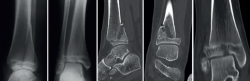

El 65,2% de los pacientes (30 casos) se trataron de forma conservadora, mientras que en el resto fue preciso un tratamiento quirúrgico. Precisaron una reducción artroscópica y posterior estabilización del fragmento con tornillos canulados 6 casos de fracturas triplanares (46,15%). En las fracturas de Tillaux, únicamente 1 caso se pudo manejar conservadoramente, mientras que el 80% restante fue tratado quirúrgicamente (Figura 5 y Tabla 1).

Figura 5. Imágenes de escopia tras reducción y fijación de la fractura. A: fractura de Tillaux; B y C: fractura triplanar, visión anteroposterior y de perfil.